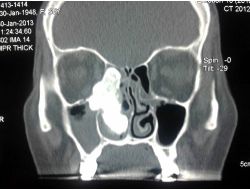

BURUN KANALINDAN CEVİZ BÜYÜKLÜĞÜNDE TÜMÖR ÇIKTI